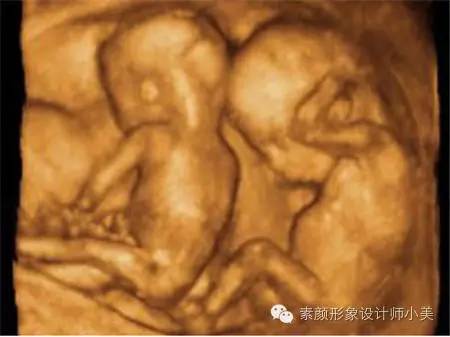

孕育课堂 (孕二十三周胎儿的发育图)

23周的胎儿看起来已经很像一个缩小的婴儿了,他(她)的身长大约20厘米,体重在450克左右。但由于皮下脂肪尚未产生,这时胎儿的皮肤是红红的,而且皱巴巴的,样子像个小老头。皮肤的折皱是给皮下脂肪的生长留有余地。